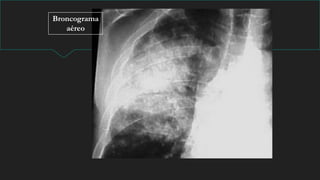

NEUMONIA

Signos Radiológicos:

 Condensación

 Broncograma aereo.

Broncograma

aéreo

NEUMONIA LOBULO MEDIO

DERECHO

Condensación basal izquierda retrocardíaca